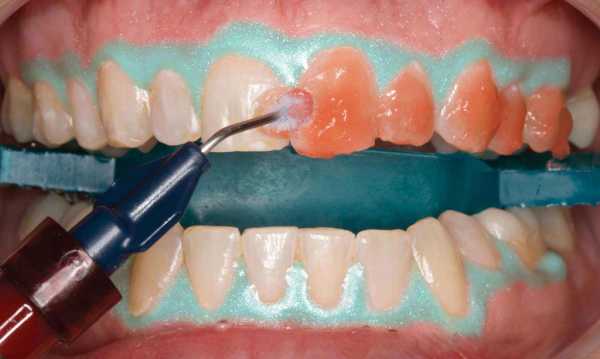

Причина 6. Отбеливающие процедуры и пасты с абразивными частицами

После процедуры отбеливания зубы могут быть более чувствительными